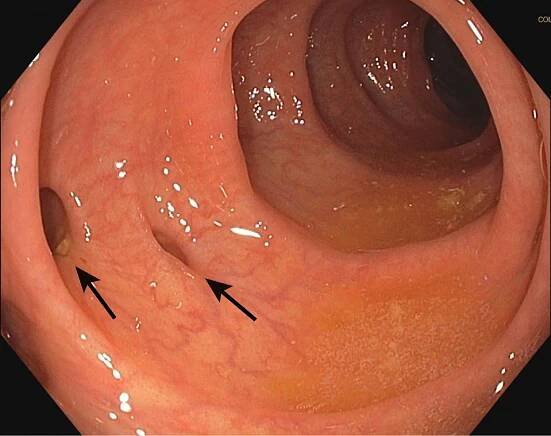

Segmental colitis associated with diverticulosis

Diverticulosis is the condition of having multiple pouches (diverticula) in the colon that are not inflamed. These are outpockets of the colonic mucosa and submucosa through weaknesses of muscle layers in the colon wall. [1 ] Diverticula do…